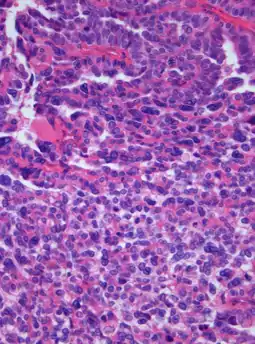

![]() | |

| Photomicrograph of hematoxylin-eosin stained section of a choroid plexus carcinoma (grade III WHO) at 400x magnification. | |